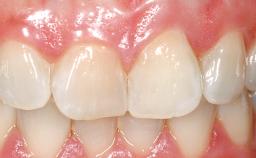

Immediate Flapless Placement of an Implant in a Maxillary Right Lateral Incisor Site

This 43-year-old male patient, a non-smoker, came to our practice because of a fracture of tooth 12 caused by a bicycle accident. Due to the combined para- and infrabony crown and root fracture, tooth extraction, and subsequent implant placement were suggested to the patient as the therapy of choice. The patient had high esthetic expectations with regard to the treatment outcome and asked for an immediate fixed provisional restoration. His individual esthetic risk profile summed up to a medium esthetic risk.

Patient's Esthetic Expectations Low Medium High

Lip Line No exposure of papillae Exposure of papillae Full exposure of mucosa margin

Periodontal Phenotype Low-scalloped, thick Medium-scalloped, medium-thick High-scalloped, thin